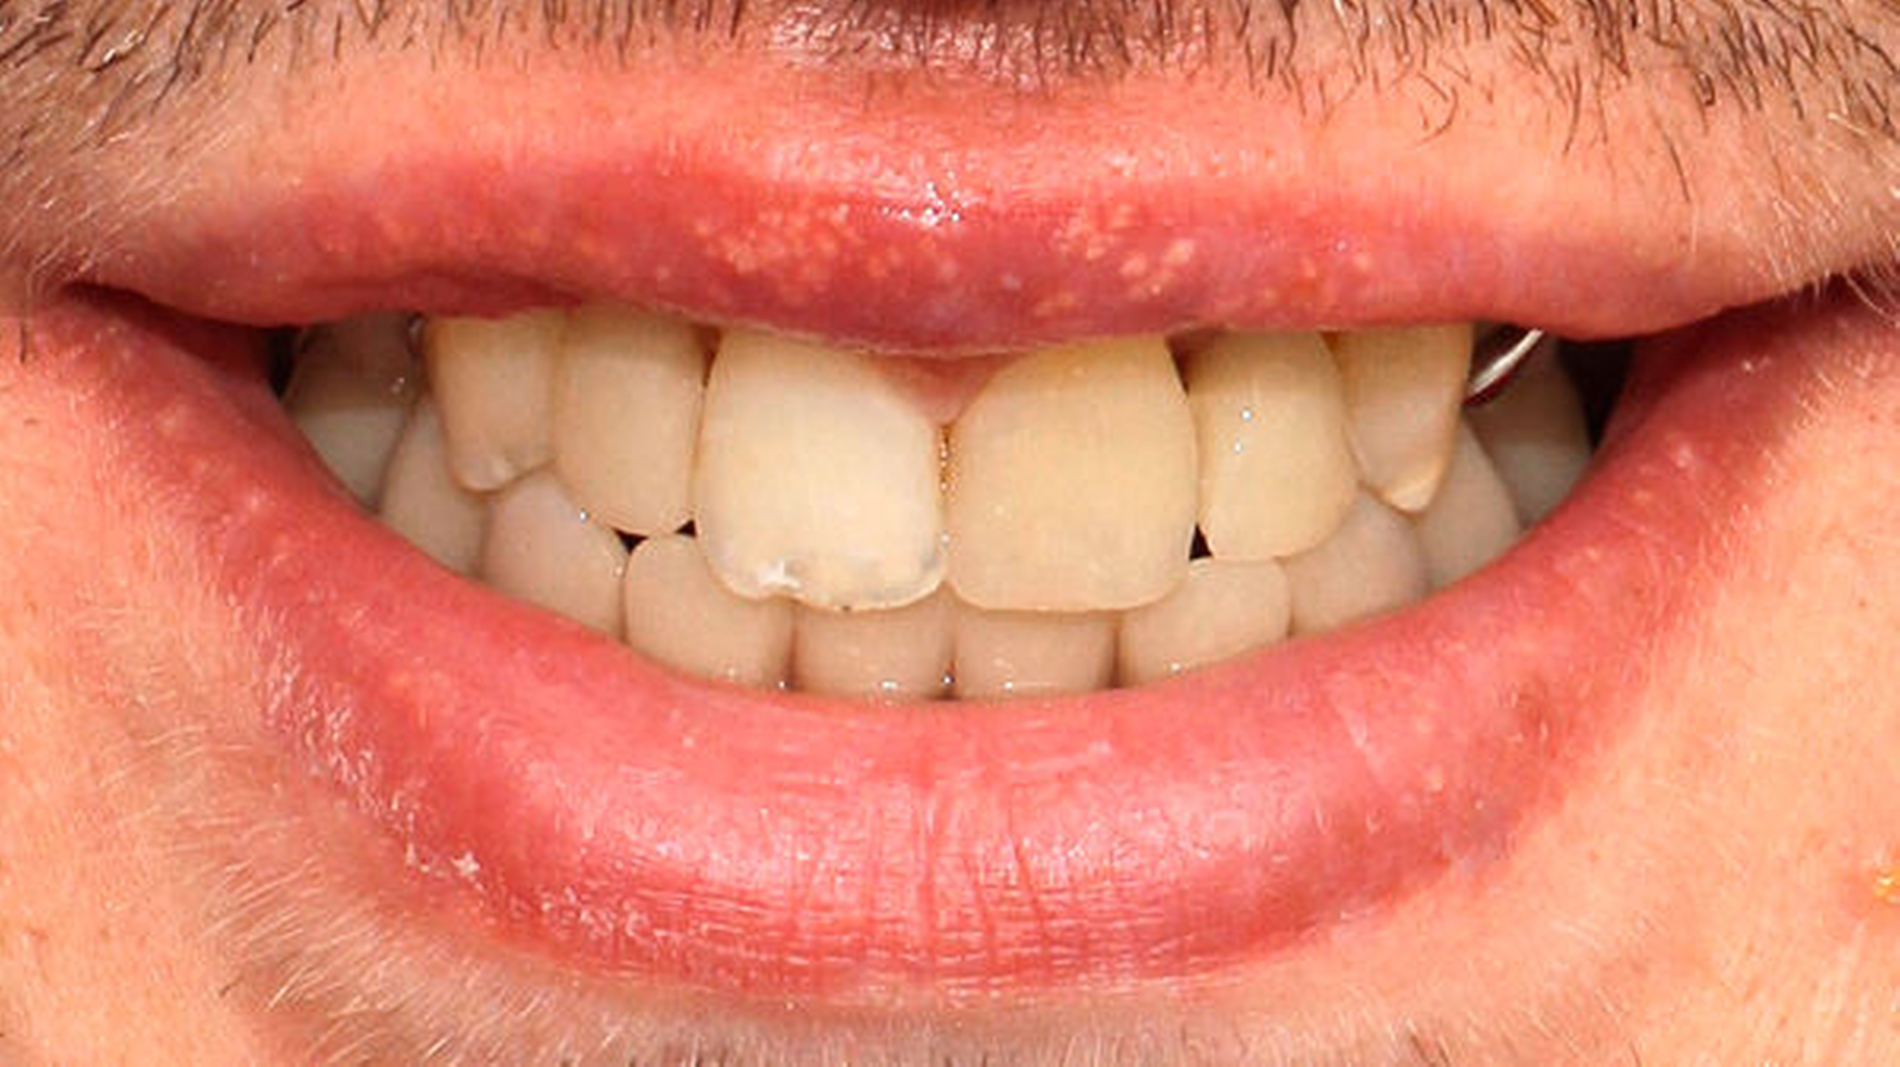

Nach Abschluss der Wundheilung wurde der definitive Zahnersatz im Unterkiefer mit einteiligen individuellen Titanteleskopen und Galvano-Sekundärteilen eingegliedert. Diese Variante bot sich durch die Notwendigkeit von angulierten Aufbauten und wegen des geringen Platzangebots an. Der obere Zahnersatz wurde der Regelversorgung entsprechend als Modellgussprothese realisiert (Abbildungen 8 und 9).